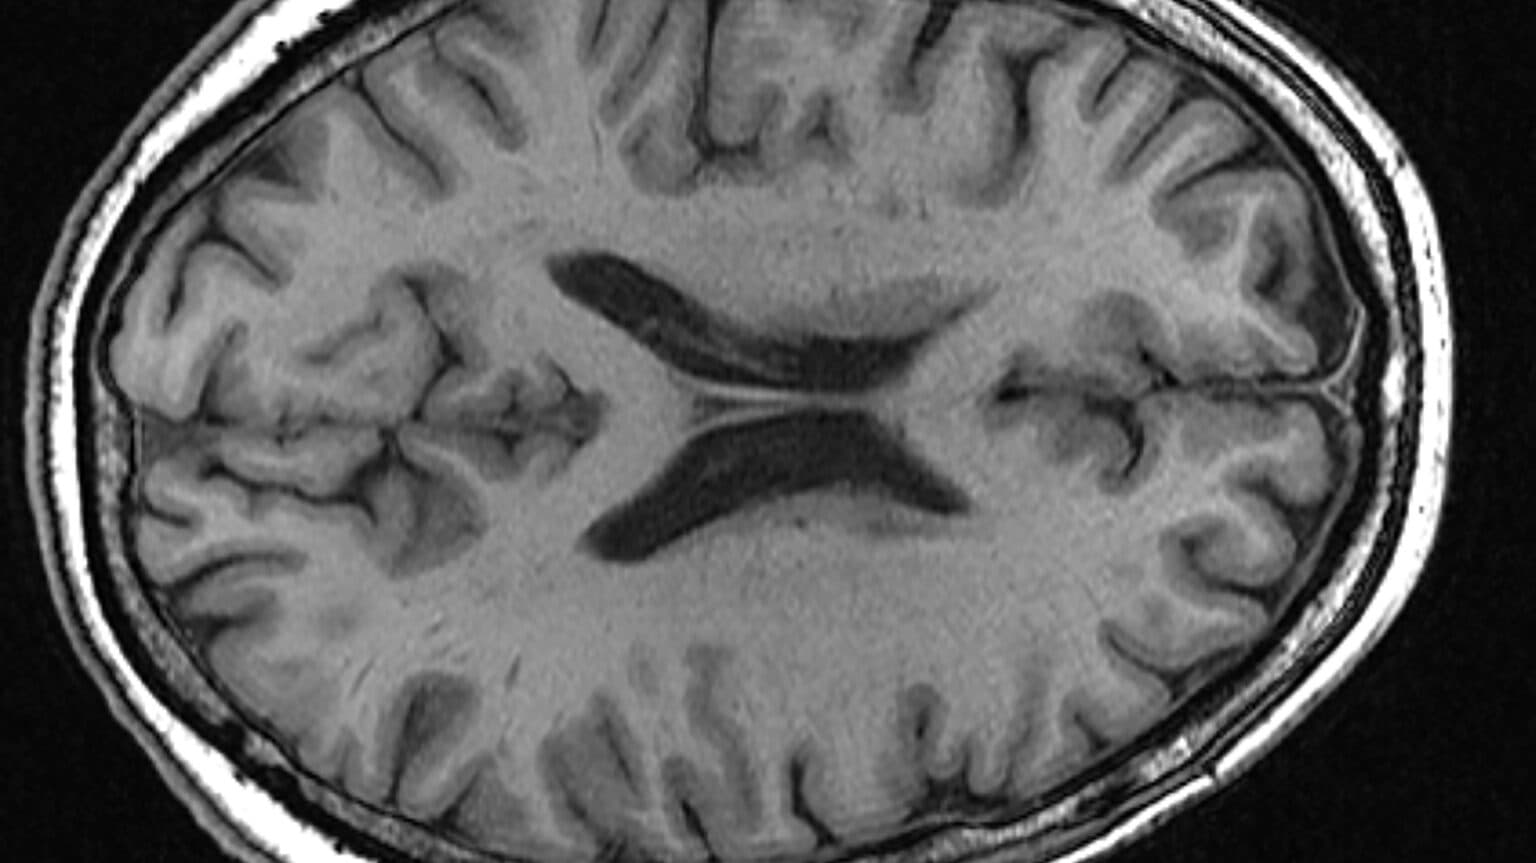

Parkinson's disease (PD) is a progressive movement disorder of the nervous system that worsens over time. It primarily affects dopaminergic neurons in the nigrostriatal circuits of the brain. The symptoms, which typically start gradually, include tremors, slowed movement (bradykinesia), rigid muscles, impaired posture and balance, loss of automatic movements, changes in speech, and alterations in writing. Nonmotor symptoms such as depression, anxiety, sleep disturbances, and cognitive issues can also occur. While there is no cure for Parkinson's disease, treatments are available to help manage symptoms.